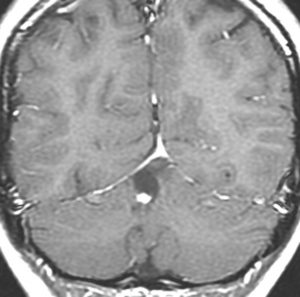

大脳皮質の毛様細胞性星細胞腫

小児期の右大脳頭頂葉にできた毛様細胞性星細胞腫です。小脳と同様に大脳にも壁在結節を作ってのう胞性増大する毛様細胞性星細胞腫というのはよくみかけます。てんかん(けいれん)発作で発症するものが多いです。腫瘍を摘出すると症候性てんかんが止まることが期待できます。治療方法は手術摘出です。腫瘍のある場所が深部で摘出術が神経脱落症状を招くと考えられる場合には,経過観察して,増大するようならガドリニウム増強される腫瘍実質部分にだけ,定位放射線治療することもあります。